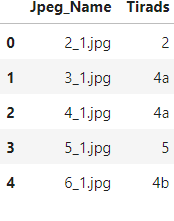

df = pd.DataFrame(data,columns =['Jpeg_Name', 'Tirads'])

return dfThe dataset is imbalanced, and several images contain thyroid cancers that are not labeled. In addition, some images have two thyroid ultrasound images from the same subject. Before algorithm training, images were processed. In data preperation ,firstly , we normalized images . Secondly, we cropped images to find to the biggest coutour of image.Also, there are text about classification of thyroid tumors on images. They were deleted because of to prevent the bias.

Let’s see df:

df.head()